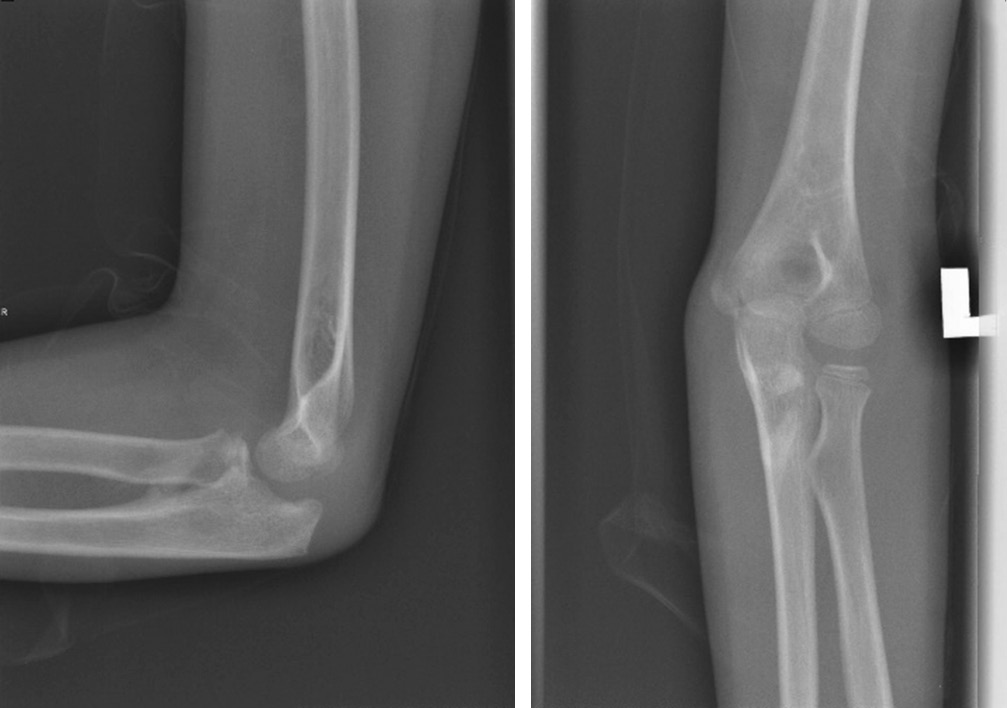

Оссификаты Локтевого Сустава: Диагностика и Лечение

Раздел: Секреты мастерства